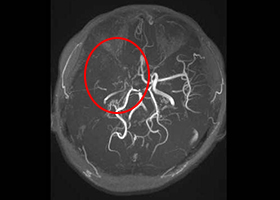

③ もやもや病に対する頭蓋内外脳血行再建術

もやもや病は原因不明の進行性脳内血管狭窄疾患であり、国によって難病指定されている病気です。典型的には小児や若年成人に起こり、脳虚血(脳梗塞)、脳出血を生じます。頭蓋内外脳血行再建術(バイパス手術)が必要な場合があります。

38歳、もやもや病、左半身一過性脳虚血発作

[画像所見]

-

右 頭部MRI -

頭部MRA(脳血管の脱落、赤丸部) 左

[手術方法]

[術後画像検査]

術前MRA -

術後MRA

術後はバイパス血管が脳内に向かって出現しています(赤丸印)。